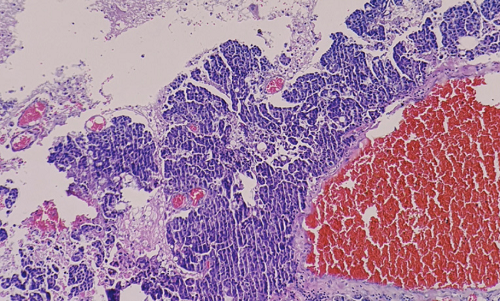

Glomangiopericytoma

A Rare Sinonasal Neoplasm

Karen Damian, Rachel Alegata

46-49

PDF